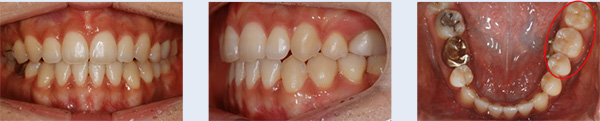

앞니 치열 불규칙하고 어금니가 잘 맞물리지 않아 소리가 나는 증상으로 내원한 22세 대학생입니다. 좌측 위 덧니가 관찰되었고 아래 어금니 배열이 바르지 않아 위 어금니와 정상적인 교합 관계를 보이지 않는 상태였습니다. 이를 빼지 않고 공간을 확보하기 위해 다음의 치료를 진행하였습니다.

① 위 치열을 측방으로 넓히기 위해 TPA(transpalatal arch, 횡구개호선) 사용

② 교정용 미니스크류(miniscrew)를 이용하여 사랑니가 있던 공간으로 위 어금니 후방 이동

③ 아래 치열 중간에 공간을 형성하기 위해 치간 삭제(interproximal stripping)

앞니 치열이 고르게 개선 되었으며 어금니가 자연스럽게 맞물리는 정상교합이 되었습니다. 자연치아를 빼지 않고 약간의 치간 삭제를 통해 교정 치료가 완료되어 환자 분의 만족도가 높은 케이스였습니다.